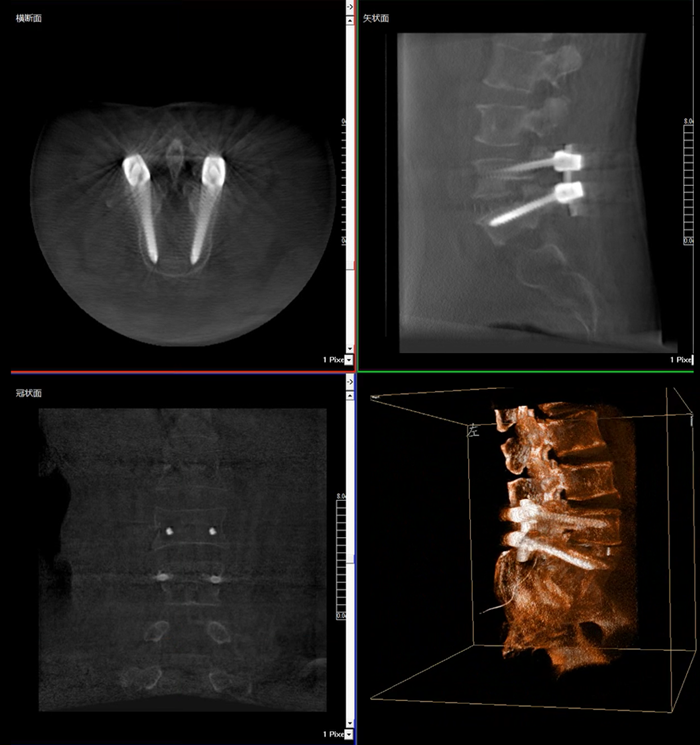

移動(dòng)式三維C形臂,又稱骨科三維C臂,就是將傳統(tǒng)二維與“類CT模式”相結(jié)合的升級(jí)版C形臂,能在術(shù)中快速地生成橫斷面、矢狀面、冠狀面斷層圖像和三維立體圖像。通過(guò)不同方位的斷層圖像,能夠更清晰、完整地顯示椎體及其附件的解剖學(xué)結(jié)果,直觀地分析病變與周圍組織的立體空間關(guān)系,三維斷層成像能夠使手術(shù)模擬和手術(shù)方案的制定更加準(zhǔn)確。

移動(dòng)式三維C形臂臨床影像

在MPR圖像中,冠狀面、矢狀面和橫斷面的信息大大提高了醫(yī)生對(duì)于病灶區(qū)以及手術(shù)效果的判定。

術(shù)中實(shí)時(shí)三維影像帶來(lái)的更加豐富的信息,可以作為醫(yī)生手術(shù)執(zhí)行的判斷基礎(chǔ),以及手術(shù)操作后實(shí)時(shí)的影像判斷依據(jù),從而保障手術(shù)效果。

在既往的手術(shù)中可能會(huì)出現(xiàn)這樣的情況:術(shù)后在影像科CT檢查中發(fā)現(xiàn)某個(gè)手術(shù)效果需要調(diào)整,這時(shí)往往需要返臺(tái)、翻修等才能解決。而移動(dòng)式三維C形臂提供的術(shù)中三維影像功能可以將這一步驟合并至手術(shù)流程中,有效地降低醫(yī)患雙方的風(fēng)險(xiǎn),為手術(shù)保駕護(hù)航。